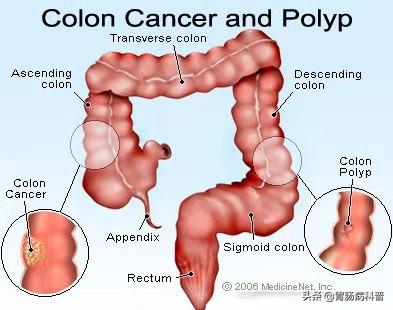

肠息肉就是肠道黏膜上所有隆起性的病变的总称,从结肠黏膜表面突出到肠腔的息肉状病变,通俗地说,就是肠道上长了一些肉疙瘩,人体的整个消化道都可以有息肉生长,其中以结肠和直肠息肉为最多,小肠息肉比较少。在未确定病理性质前均称为结肠息肉。

结肠息肉与结肠癌的关系密切,大约80-95%的结直肠癌是结直肠息肉演变而来。

所以,临床上一经发现,一般都需要切除以绝后患。